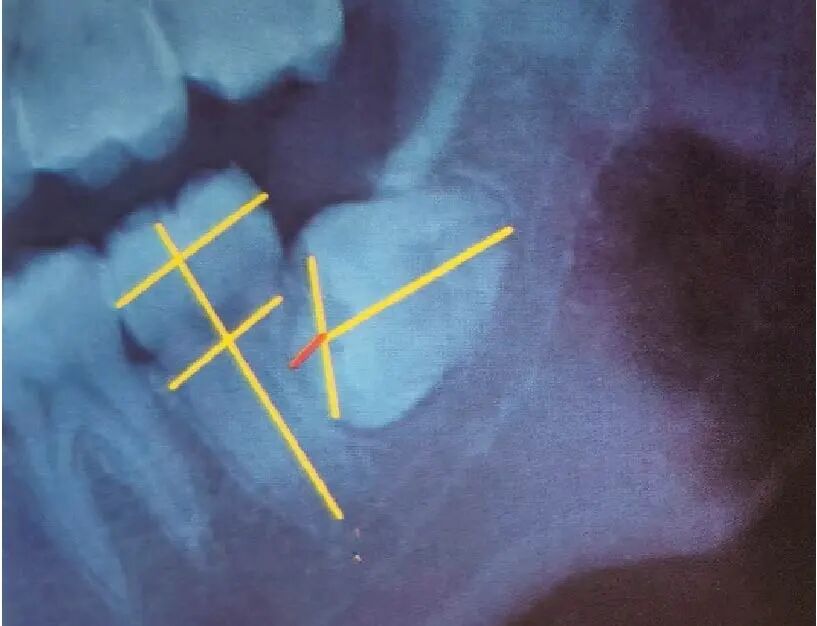

下颌阻生齿的常见分类

下颌近中倾斜

高位阻生

在下颌第二磨牙中冠部外形高点以上部分为高位。

中位阻生

冠部外形高点线与髓室底之间部位为中位。